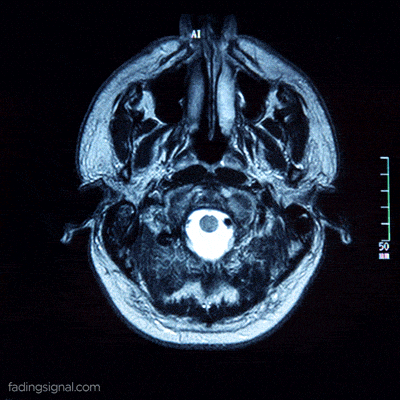

medical school brain GIF